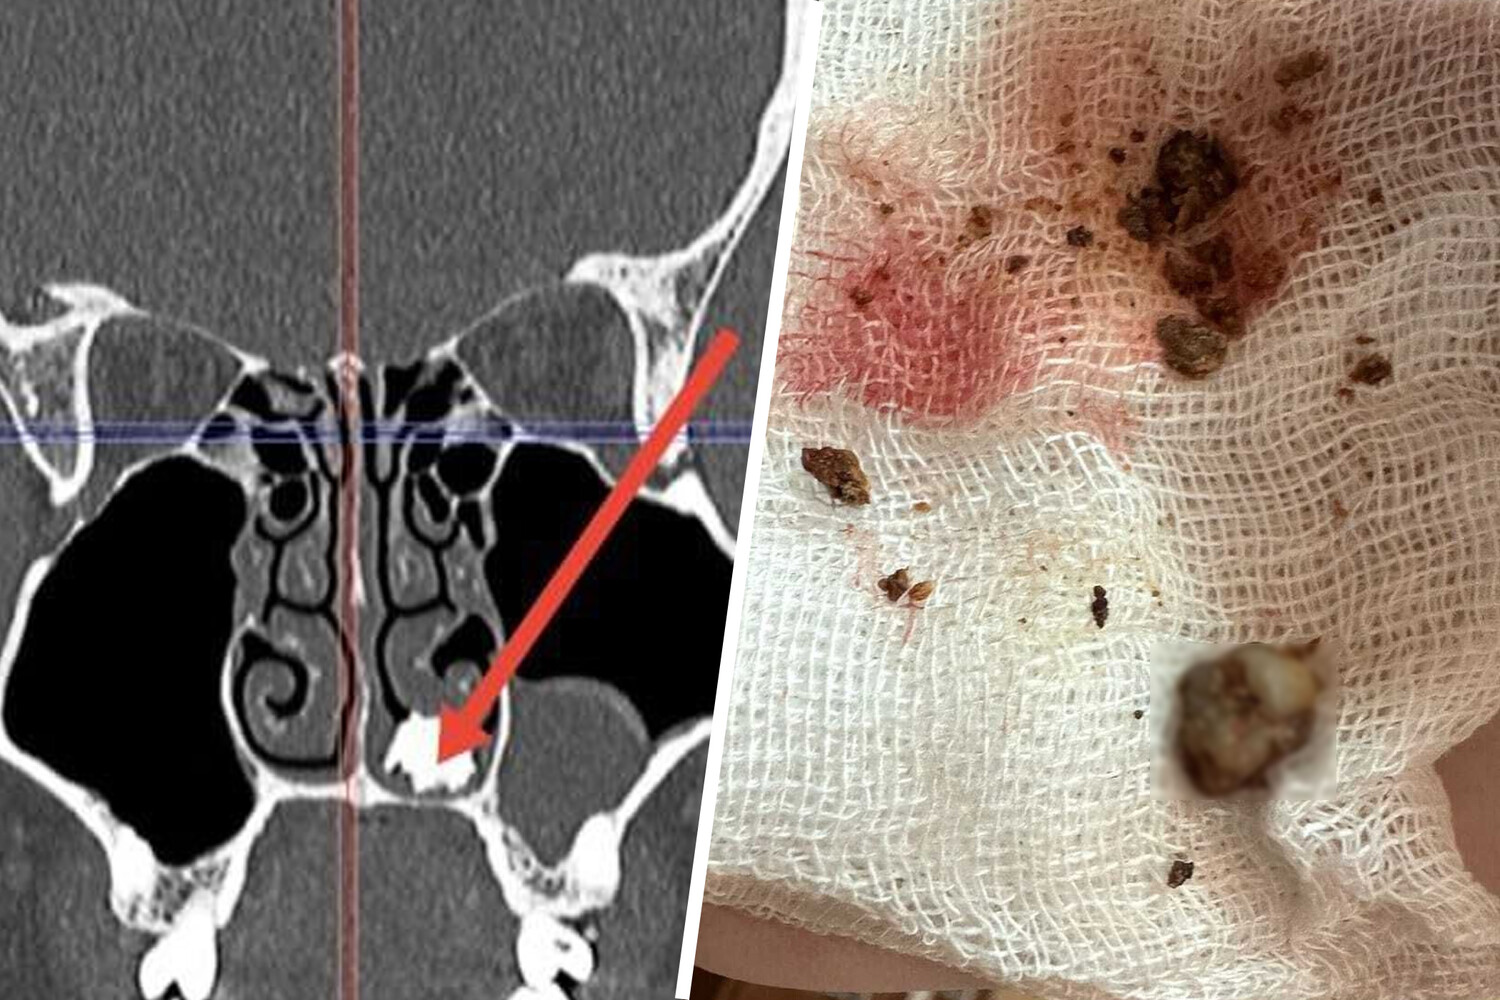

В Московской области врачи извлекли молочный зуб из носа 22-летнего молодого человека, который жаловался на затяжной насморк. Об этом сообщили в пресс-службе регионального Минздрава.

Пациент обратился к медикам Долгопрудненской больницы. Он рассказал, что его беспокоит насморк, который не получается вылечить продолжительное время. Во время обследования медики нашли в полости носа пациента костное образование. Юношу направили на операцию.

Во время нее отоларингологи извлекли из носа молочный зуб, покрывшийся грибковым содержимым — медики предположили, что зуб находился в носу много лет.

«Видимо, 10 лет назад его и не досчиталась зубная фея», — пошутили в пресс-службе ведомства.

После операции пациент несколько дней находился под присмотром врачей. Сейчас молодого человека уже выписали.